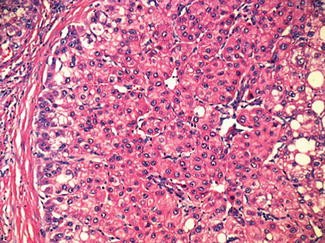

Hepatocellular carcinoma (HCC) and other major types of . . .

Introduction and methods: Hepatocellular carcinoma ( HCC ) remains a difficult disease to study even after a decade of genomic analysis . Metabolic and cell-cycle perturbations are known, large changes in tumors that add little to our understanding of the development of tumors, but generate "noise" that obscures potentially important smaller scale expression changes in "driver genes" .

WritePass - Essay Writing - Dissertation Topics [TOC]AbstractChapter 1 Hepatocellular Carcinoma1 .1 Introduction1 .2 MethodologyChapter 2 Hepatocellular Carcinoma2 .1 Anatomy and Physiology of the Liver2 .2 Incidence of HCC2 .3 Aetiology of HCC2 .4 Pathology of HCC2 .4 Clinical Presentation and Symptoms of Hepatocellular CarcinomaChapter 3 Hepatocellular Carcinoma3 .1 Diagnostic Pathway3 .1 Staging of . . .